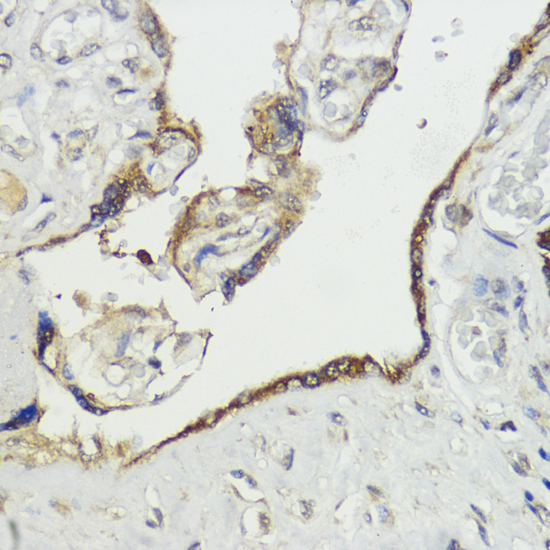

Immunohistochemistry of paraffin-embedded human placenta using HACE1 at dilution of 1:100 (40x lens).

Immunohistochemistry of paraffin-embedded rat testis using HACE1 at dilution of 1:100 (40x lens).